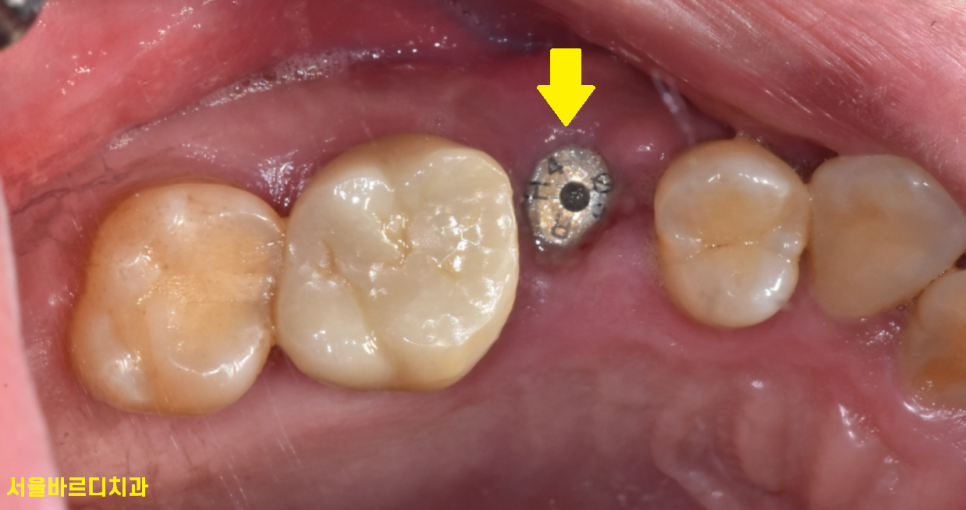

231117

풍산동 치과 방문하신 날

어금니 쪼개짐 치아 발치

그리고 임플란트 진행하였습니다.